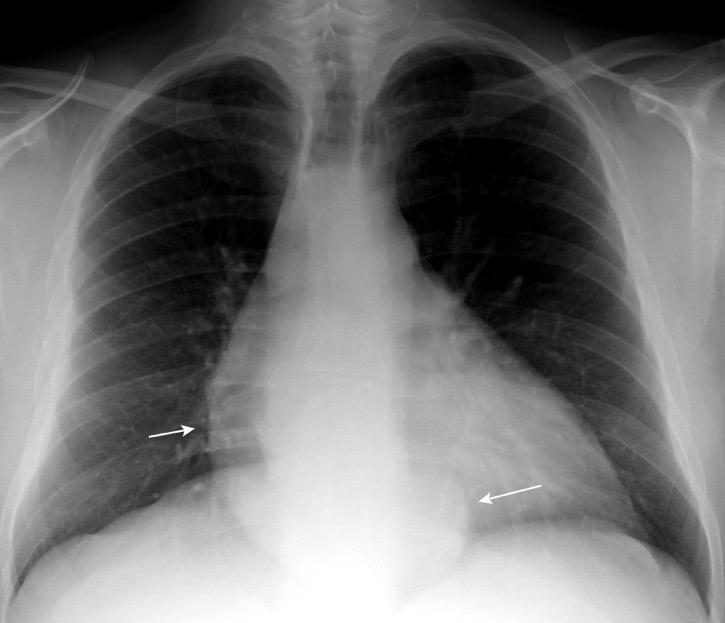

Líneas paraespinales formando un “paréntesis” por encima del diafragma. El signo señala el origen “intratorácico” de la lesión.

Conrad A et al. Pott’s disease associated with large and multiple abscesses in a 30-year-old migrant from Chad. BMJ Case Rep 2018

(lesiones toracoabdominales) La divergencia de las líneas paraespinales apunta a lesión toracoabdominal, que desde el tórax desciende y penetra en el abdomen.

Signo del “iceberg” positivo en Tb vertebral

Afectación por vía hematógena. Región dorsolumbar más frecuente. Afectación inicial: irregularidad de los platillos vertebrales, disminución del disco intervertebral con esclerosis ósea adyacente. Kim. Radiographics.2001